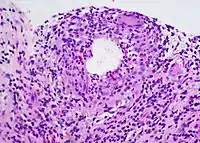

Diagnosis

A chalazion or meibomian cyst can sometimes be mistaken for a stye.

Differential diagnosis

- Sebaceous gland adenoma

- Sebaceous gland carcinoma

- Sarcoid granuloma

- Foreign body granuloma

Chalazia may recur, and they will usually be biopsied to rule out the possibility of a tumour.[4]